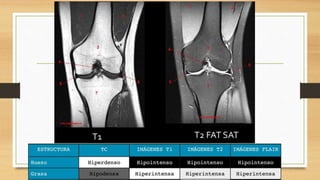

EXAMENES AUXILIARES

Linea de Blumenssat,

cicatriz del cartílago

hialino